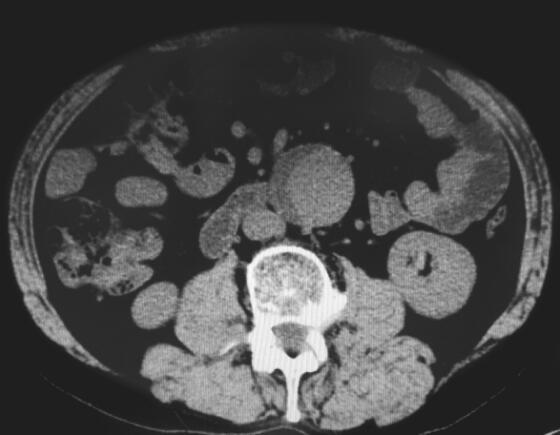

1小时条评论老年男性,因间断胸闷憋气5年,加重7天前来就诊。既往吸烟史,否认高血压及糖尿病病史。5年前外院行冠脉造影检查,未见冠脉明显狭窄,发现腹主动脉瘤7个月。 此次以胸闷憋气,发作诱因不明显,CTnI轻度升高,发作时心电图表现为心律失常和ST-T改变,但复查冠脉造影...